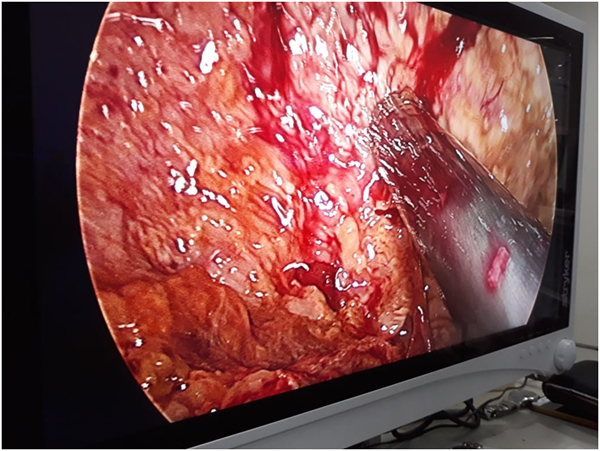

A Young lady who was a small kid...when her mother was operated for a Complex Gastrointestinal condition almost 14 years back by Dr Suddhasattwa Sen suddenly came in with severe blood loss from Gastrointestinal tract with a loss of almost 2 to 3 litres of blood with Shock with fainting . Further stabilisation was done and then extensive investigation revealed not only Piles and GI Ulcers but also SRUS Bleeding ulcers in rectum. A condition called Solitary Rectal Ulcer Syndrome ( a complex and difficult to cure anorectal problem ) . Her hemoglobin dropped to below 7 gm% She finally underwent surgery after 5 days and left home after 2 days post op without any further bleed or problems .